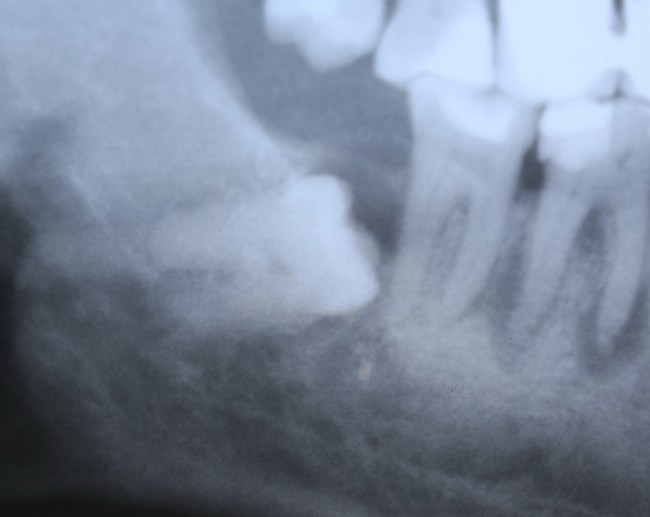

Несколько лет назад он сделал панорамный снимок (собирался лечить зубы), на котором выявили ретинированный зуб мудрости — обычное дело, между прочим.

Предложили его удалить. Но Егор отказался, мотивируя это тем, что зуб не болит, не беспокоит и никак не мешает.

Примерно через три года снимок повторили — уже по другому поводу:

И что мы видим? Под зубом образовалась гигантских размеров фолликулярная киста. То есть, теперь нам нужно не только удалять ретинированный зуб мудрости, но и фолликулярную кисту. А для этого, кстати, придется депульпировать соседний седьмой зуб:

то есть, вместо пустячного и своевременного удаления ретинированной восьмерки, мы получили серьезную проблему, которая, к счастью разрешилась, благодаря случайно сделанному панорамному снимку и вовремя проведенному хирургическому вмешательству.